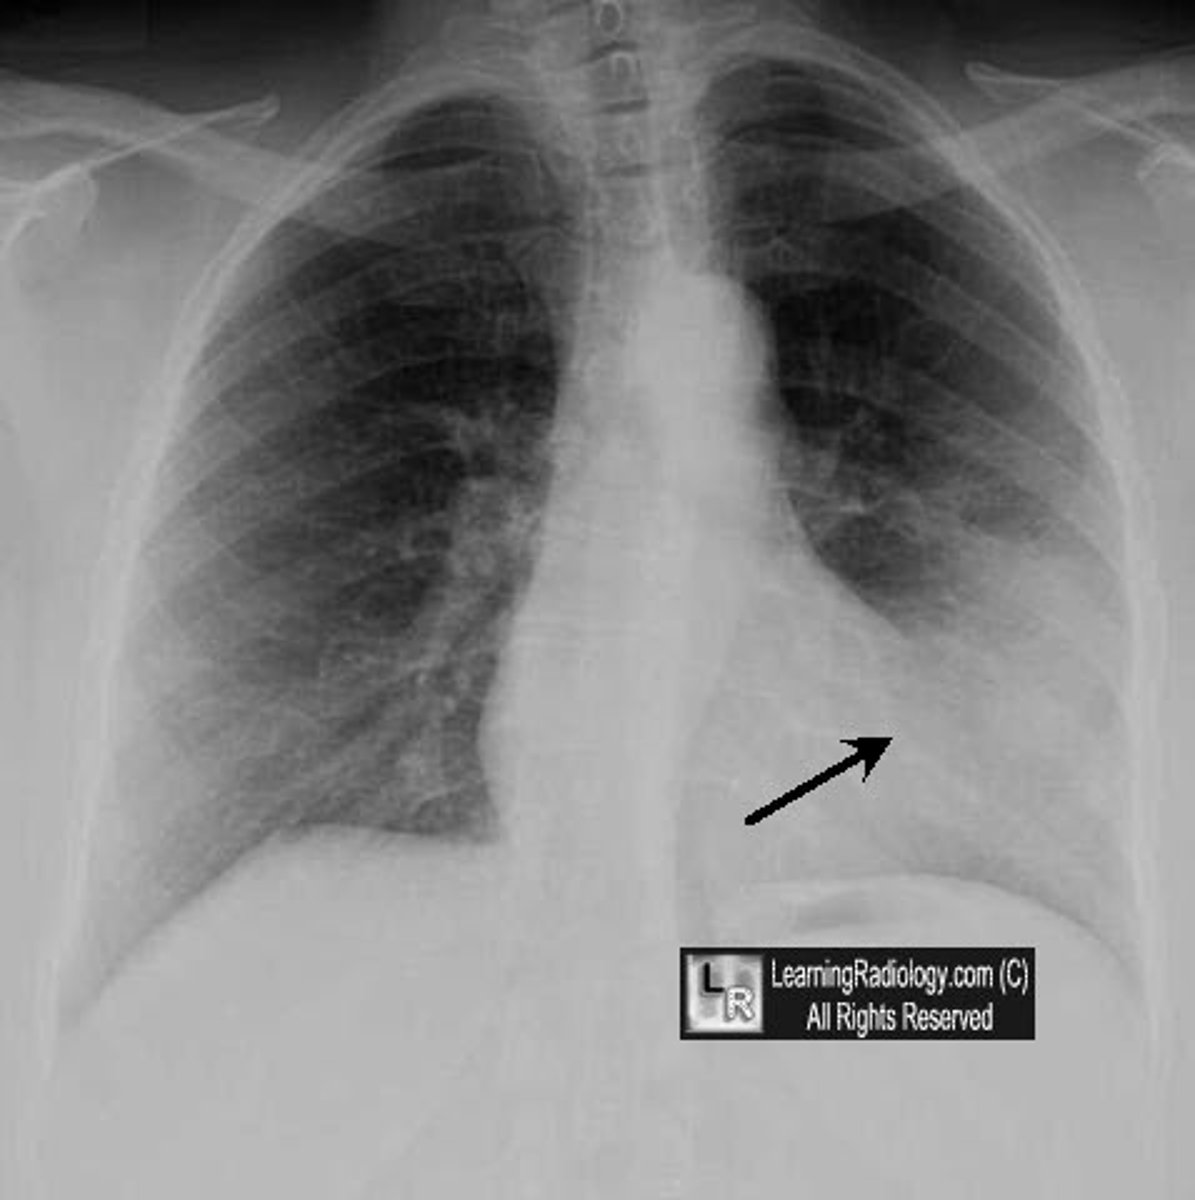

right boarded of the heart

convex shape, formed by right atrium (on x-ray)

left boarder of the heart

almost vertical, formed mainly by the left ventricle (on x-ray)

inferior boarded of the heart

horizontal, formed mainly by right ventricle (on x-ray)

superior boarder of the heart

boarder above the heart (on x-ray)